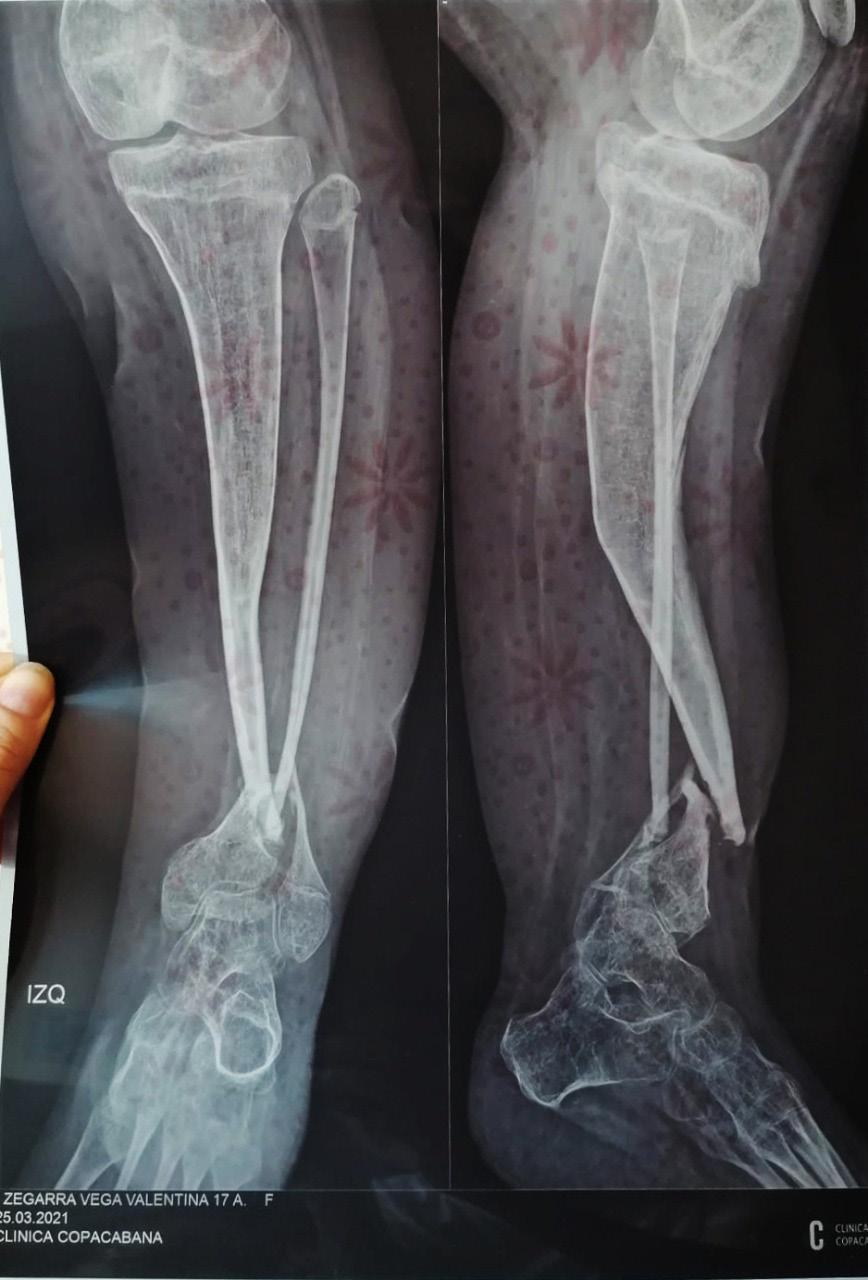

Uso de terapia de cierre asistido por vacío artesanal para el tratamiento de defecto de partes blandas en paciente postoperado de osteomielitis crónica en tibia

Use of artisanal vacuum-assisted closure therapy for the reatment of soft tissue defects in a postoperative patient with chronic tibial osteomyelitis

Eduardo Monasterios, Alvaro Mamani, Cristian Mostacedo